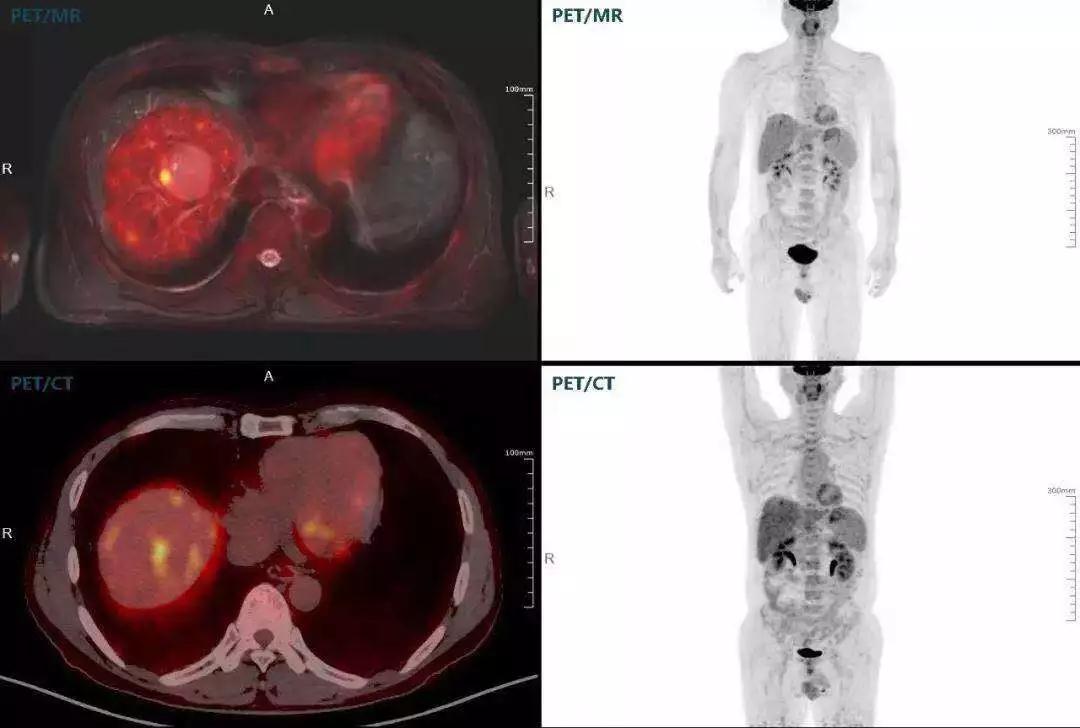

肝癌

聯(lián)影“時(shí)空一體”超清TOF PET/MR搭載的壓縮感知技術(shù),能夠同時(shí)實(shí)現(xiàn)16期成像,精準(zhǔn)捕獲肝臟動(dòng)態(tài)影像的每一瞬間,同時(shí)兼顧早期與晚期等全部期相的完整病灶信息,實(shí)時(shí)、全方位鎖定病灶。同時(shí),基于其2.8mm超高分辨率,能夠精細(xì)呈現(xiàn)腫瘤邊界信息,捕捉局部微小病灶與遠(yuǎn)端轉(zhuǎn)移灶,助力醫(yī)生精準(zhǔn)診斷。

(對(duì)于同一例肝臟惡性腫瘤,PET-CT與PET/MR成像對(duì)比??梢钥吹剑?lián)影PET/MR圖像對(duì)腫瘤邊界和FDG高濃聚區(qū)域清晰顯示。)